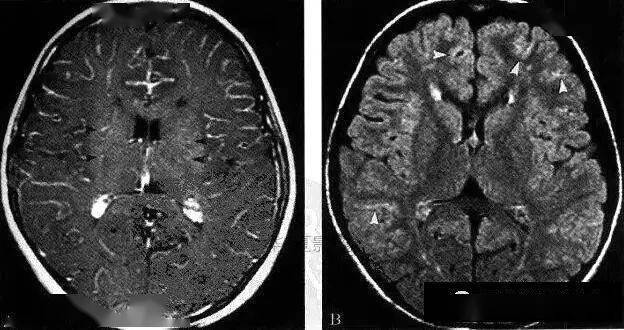

【影像病理】烟雾病(moyamoya disease),ct及mri表现

图片尺寸500x509